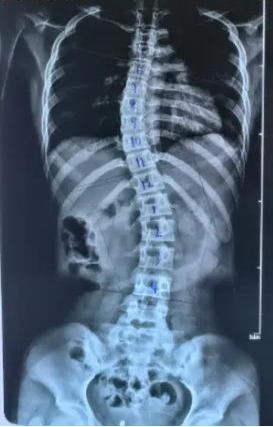

健康科普|青少年特发性脊柱侧弯,早发现早干预很重要

你家孩子站立时双肩是否等高?行走时是否习惯性倾斜身体?这些看似不起眼的细节,可能隐藏着“青少年特发性脊柱侧弯”风险。作为继肥胖、近视之后危害我国儿童青少年健康的第三大疾病,“青少年特发性脊柱侧弯”正悄然威胁着孩子们的成长。

“青少年特发性脊柱侧弯”的危害远不止影响体态美观。除了导致高低肩、剃刀背等影响体态美观的问题,它还会直接挤压胸腔空间,进而影响孩子的心肺功能——不少患病孩子会出现运动耐力下降、稍活动就呼吸不畅的情况。

早期自我检查是及时发现异常的关键,家长和孩子可以通过以下简单方法初步判断: 1.观察身体对称性:让孩子站立,查看双肩是否等高、一侧肩胛骨是否隆起,腰部两侧是否对称、骨盆有无倾斜; 2.Adam前屈试验(弯腰测试):孩子双脚并拢、双臂自然下垂,缓慢向前弯腰至90度,观察背部是否出现不对称的隆起或凹陷; 3.日常活动观察:留意孩子行走或站立时是否习惯性倾斜身体,衣物是否因脊柱侧弯出现不对称的褶皱或磨损。 不过,自我检查需注意以下几点: 一是定期检查:建议每3-6个月做一次,尤其是青春期快速发育阶段,脊柱变化较快。 二是避免误判:轻微不对称可能是姿势不良或肌肉紧张导致,需结合专业评估,自我检查不能替代医生诊断,确诊需依赖全脊柱X光片。 三是早期干预:轻度侧弯可通过姿势矫正、运动康复改善,中重度侧弯可能需要支具或手术治疗,早发现、早干预是降低危害的核心。 如果出现以下情况,务必及时带孩子就医: 自我检查发现明显不对称或弯腰测试异常; 孩子经常主诉背部疼痛、疲劳或活动受限; 家族中有脊柱侧弯病史。 这些信号提示可能存在脊柱问题,需尽快由专业医生诊断。 脊柱是人体的“成长支柱”,关乎孩子一生的健康。家长朋友们,别让忽视成为孩子成长的遗憾——从今天起,定期为孩子做脊柱检查,关注他们的体态变化,让我们共同守护孩子的脊柱健康,为他们的未来筑牢“健康支柱”。 科普医生简介 刘丙科 骨外科副主任医师,脊柱外科副主任。 毕业于广东医科大学,曾先后到中山大学附属第一医院脊柱外科、中山大学附属孙逸仙纪念医院脊柱微创中心进修学习。发表专业论文7篇,主持完成阳江市科研立项2项。广东省医院协会脊柱外科专业委员会第一届委员、广东省健康管理学会脊柱专业委员会第一届青年委员会、广东省基础医药学会骨科修复重建专业委员会第一届委员、广东省中西医结合学会骨科微创专业委员会第三届委员会委员、广东省医疗行业协会脊柱外科管理分会委员、广东精准医学应用学会脊柱脊髓病分会第一届委员、阳江市医学会脊柱外科学分会第一届委员会委员。 擅长领域:对脊柱各类疑难疾病诊治有丰富的临床经验,擅长颈胸腰椎管减压、椎间盘切除、椎体滑脱或骨折复位、椎间植骨融合、椎体病灶清除、椎弓根螺钉内固定术等传统手术,并擅长经皮椎体成形术(PVP)、经皮椎体后凸成形术(PKP)、选择性神经根阻滞术、脊柱内镜辅助下髓核摘除术、射频消融术等微创技术。 门诊坐诊时间、地点: 时间:周三下午、周六全天。 地点:2号楼2楼40号诊室。